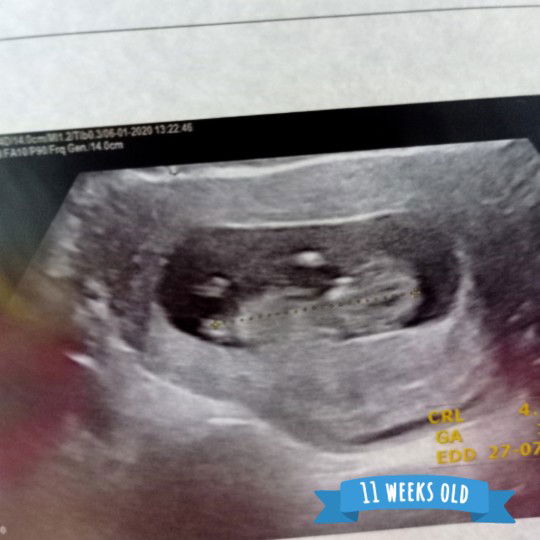

ขอดูแม่ๆ 11 week หน่อยค่าาาา☺

เจ้าตัวน้อยของแม่ๆท่านอื่นโตขนาดไหนกันบ้างแล้วค่ะ? # ในภาพซาว 11 ตอนนี้ 13 week แล้วงับ??

ตอน11วีคค่ะ